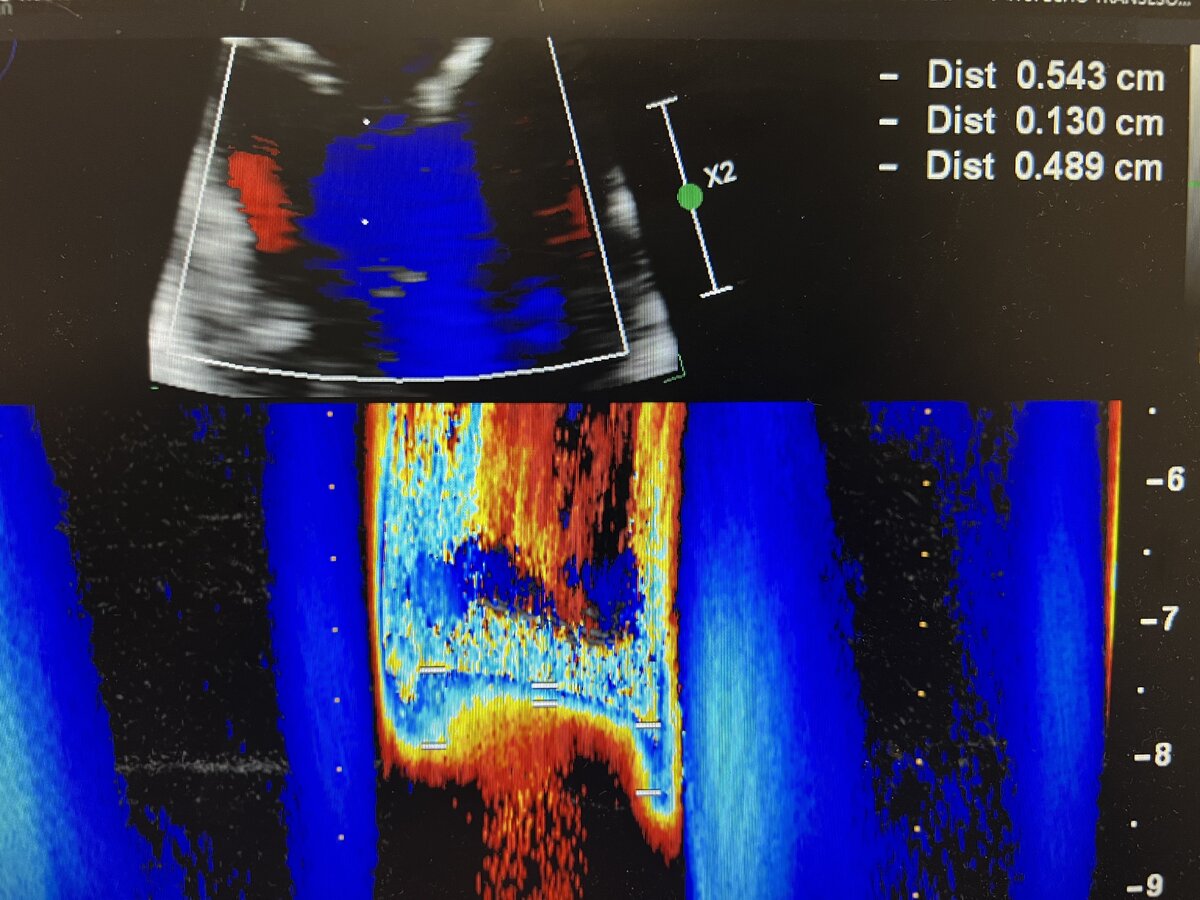

I love this series of clips- particularly the last picture, which nicely illustrates one of the (many) fundamental flaws of PISA, despite apparent agreement with 3D VCA in this case. Any current fellows want to explain what I’m getting at, particularly with the last picture? Do you think the “real” MR severity is more or less than what I’ve calculated here?

I'm not an ACTA fellow, but I'm studying for my basic so I'll take a stab (also I love this thread). PISA makes the assumption that your MR jet is holosystolic. I think that your last photo is showing color / aliasing over time for your MR jet showing that it actually does vary (looks like it's higher at beginning and end systole).

My suspicion is this is overestimating your MR, since it's assuming the PISA you measured is consistent throughout but your photo shows that's clearly not true.

Bingo! You can actually measure the “area under the curve” in the last color M-mode shot and integrate that value to get a time-weighted “average” PISA radius over the course of systole, but you need special software to do this offline (and frankly it’s not really worth it outside of maybe some research settings).

You can also predict based on the color M-mode picture that this was functional MR, which is worse in early and late systole (since this is when the LV volume is larger, and therefore leaflet tethering is greatest). Primary MR (as with a flail leaflet) usually has an accelerating color M-mode signature that shows the MR ramping up and reaching maximum severity in mid-late systole when the ventricle is smallest, and therefore the excursion of any prolapsing leaflet tissue is maximal